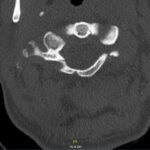

The Jefferson fracture classification system describes fractures of the atlas (first cervical vertebra or C1). Jefferson fractures with potential tears in the transverse ligament can cause cervical spine instability and can result in neurologic injury if not appropriately diagnosed and managed. We present the case of a 54-year-old man who fell head first with cervical spine tenderness and upper extremity paresthesias. The patient’s Jefferson fracture was diagnosed via computed tomography. The patient was then treated non-operatively for his Jefferson fracture, and he had an unremarkable hospitalization. Emergency physicians should obtain surgical consultation and consider the possibility of ligamentous injury in patients suffering injury to the cervical spine.